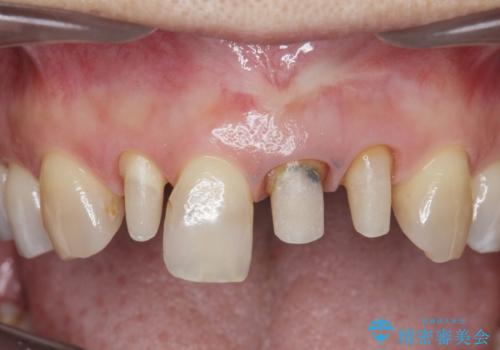

- 前歯のクラウンの歯肉の位置が年々変化し、歯ぐきのフチが黒くなってしまった、綺麗にしたいと希望されて来院されました。

装着されているセラミッククラウンを除去したのち、現在の歯ぐきのラインにしっかりと合う精度の高いオールセラミッククラウンを作製していきます。

- 39.6万円(ジルコニアクラウン×3・仮歯×3)費用は治療当時の料金となります